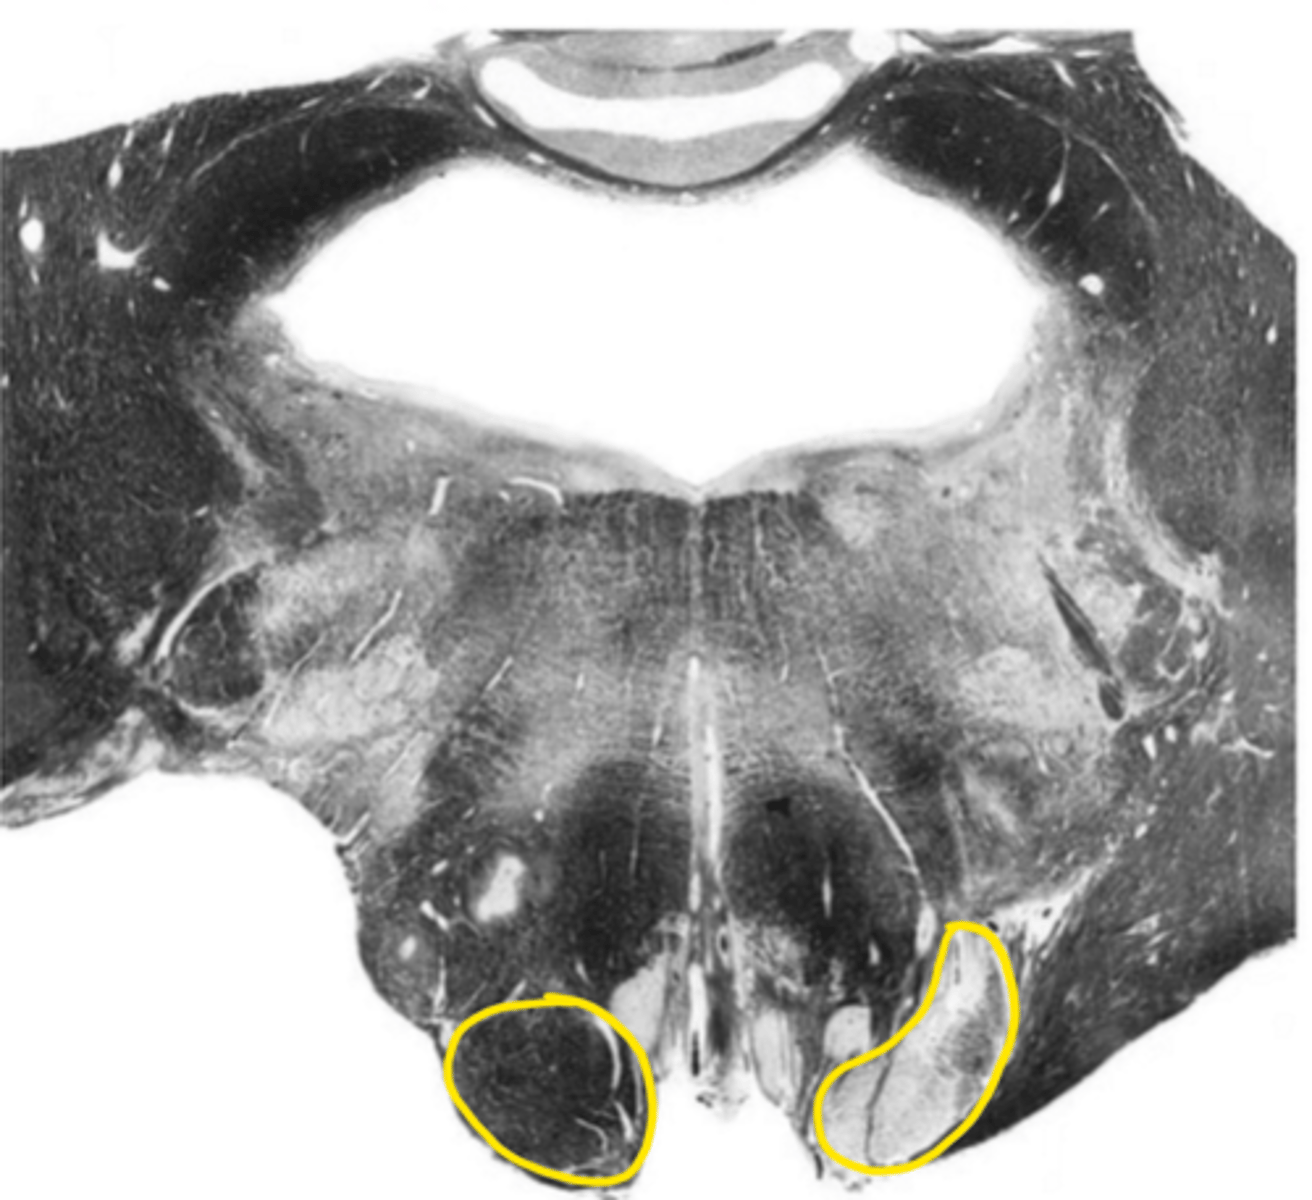

olive

ID the structure

principle olivary nucleus

corticospinal fibers

anterior median sulcus

vestibular nucleus

ID the nucleus

foramen of Luschka

ID the space

cochlear nucleus

glossopharyngeal nerve

ID the nerve

fourth ventricle